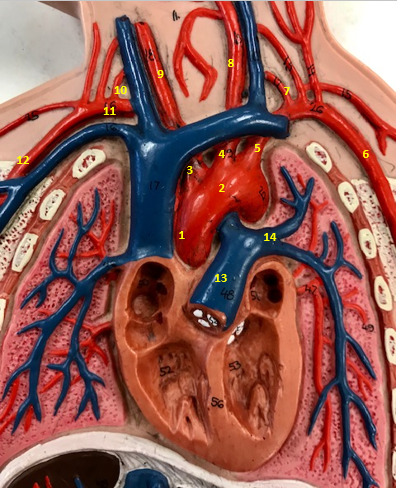

Aorta

Name #2

Brings blood out of left ventricle

Function of aorta

Brachiocephalic artery

Name #3

Supplies oxygenated blood to right arm shoulder neck and head

Function of brachiocephalic artery

Left common carotid artery

Name #4

Supplies oxygenated blood to left neck and head

Function of left common carotid artery

Left subclavian artery

Name #5

Supplies oxygenated blood to left arm shoulder

Function of left subclavian artery

Left axillery artery

Name #6

supplies blood to left armpit and upper limb

Function left axillary artery (6)

Left vertebral artery

Name #7

Supplies blood to brain and spinal cord

Function of left vertebral artery (7)

Left common carotid artery

Name #8

Supplies blood to left neck and head

Function of left common carotid artery (8)

Right common carotid artery

Name #9

Supplies oxygenated blood to right neck and head

Function of right common carotid artery (9)

Right vertebral artery

Name #10

Supplies blood to brain and spinal cord

Function of right vertebral artery (10)

Right subclavian artery

Name #11

Supplies blood to right arm and shoulder

Function of right subclavian artery

Right axillery artery

Name #12

Supplies blood to right armpit and upper limb

Function of right axillery artery (12)

Pulmonary trunk

Name #13

Bring blood out of right ventricle to lungs

Function of pulmonary trunk (13)

Left pulmonary artery

Name #14

Bring blood to left lung

Function of left pulmonary artery (14)